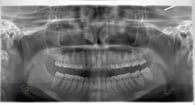

初診の場合は全体を診るためのパノラマX線写真